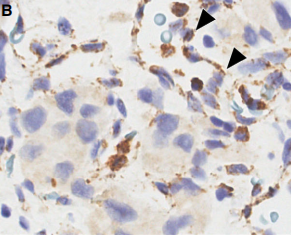

- SDHB标记: SDHA/B/C/D/AF2基因(统称SDHx)的突变或甲基化均可导致SDHB蛋白表达异常(缺失或减弱)。SDHB表达异常提示可能存在SDH缺陷相关的遗传性肿瘤综合征。本例患者SDHB蛋白表达正常。

SDHB免疫组化结果判读示例:A图为正常表达(胞浆颗粒状强阳性),B-F图均为不同模式的表达异常 [引自PMID:35546442]